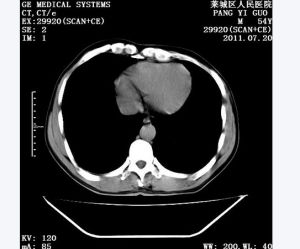

位置較表淺的海綿狀血管癌,局部皮膚膨隆,高低錯落,起伏不平,皮面微現藍色或淺紫色,曲張盤鏇的血管隱約可見。海綿狀血管癌位置較深而不波及皮膚者,除局部顯現形態不規則的輕、中度膨隆外,膚色並無明顯改變。海綿狀血管癌也可見於黏膜下層,黏膜表面呈暗藍色改變。腫物有壓縮性,其體積大小可隨體位改變而發生變化。觸診檢查有似蠕蟲盤繞聚集之感,或可捫出顆粒狀靜脈石存在,X線照片也可顯現靜脈石,此乃血栓機化鈣鹽沉著而形成。海綿狀血管癌好發於頭、面、頸部,四肢、軀幹次之。除常見於皮膚皮下組織外,偶見於黏膜下,也可發生在肌肉、骨骼和內臟器官內。

多在出生時即已發現,或起病隱伏而難以準確追溯發病年月。海綿狀血管癌還可發生於肌肉組織內,稱為肌間血管癌,以股四頭肌最常累及,易被誤診;有時累及骨骼,表面粗糙不平,如蟲咬狀,累及骨髓腔者,X片中可見骨小梁被破壞後的多腔空泡樣徵象。上、下頜骨的海綿狀血管癌發病率雖不高,但應予重視,有時因拔除一個鬆動的牙齒可導致致命性的大出血。當血管癌受外界刺激時,可引起血管周圍組織炎性反應,患者自覺皮膚發熱、腫脹、疼痛,或在病灶表面發生破潰。有血栓或靜脈石形成時,也可出現局部疼痛,疼痛往往為一過性,短則一天,長則數周,以後自行緩解。在受外傷或表面破潰感染時,可引起出血危險。多數海綿狀血管癌是局限性的,少數瀰漫地累及大片組織,如四肢的海綿狀血管癌,是血管癌治療中的難點。 成人海綿狀血管癌的診斷較為明確,可在嬰幼兒期到青少年期發現,多數表現為較穩定而緩慢的發展過程。關於海綿狀血管癌的本質仍然存